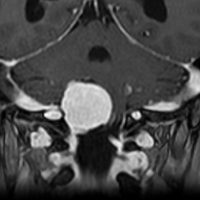

静脈洞交会髄膜腫 meningioma of the confluence of sinuses

若い女性に偶然発見されたものです。直静脈洞と静脈洞交会の接合部あたりに発生したもので,静脈洞はほぼ閉塞に近い所見でした。しかし,この部分の静脈洞は,テント硬静脈側副路が発達することがあるので,硬膜を含めた積極的な摘出をすることは絶対にできません。もしほんの少しでも流れがある直静脈洞を閉塞させると短時間に脳死になるような脳静脈圧亢進が生じる可能性があるからです。静脈洞内に少し取り残して(右下の矢印)手術を終了しました。手術後には定位放射線治療を行って再増大を防ぎます,